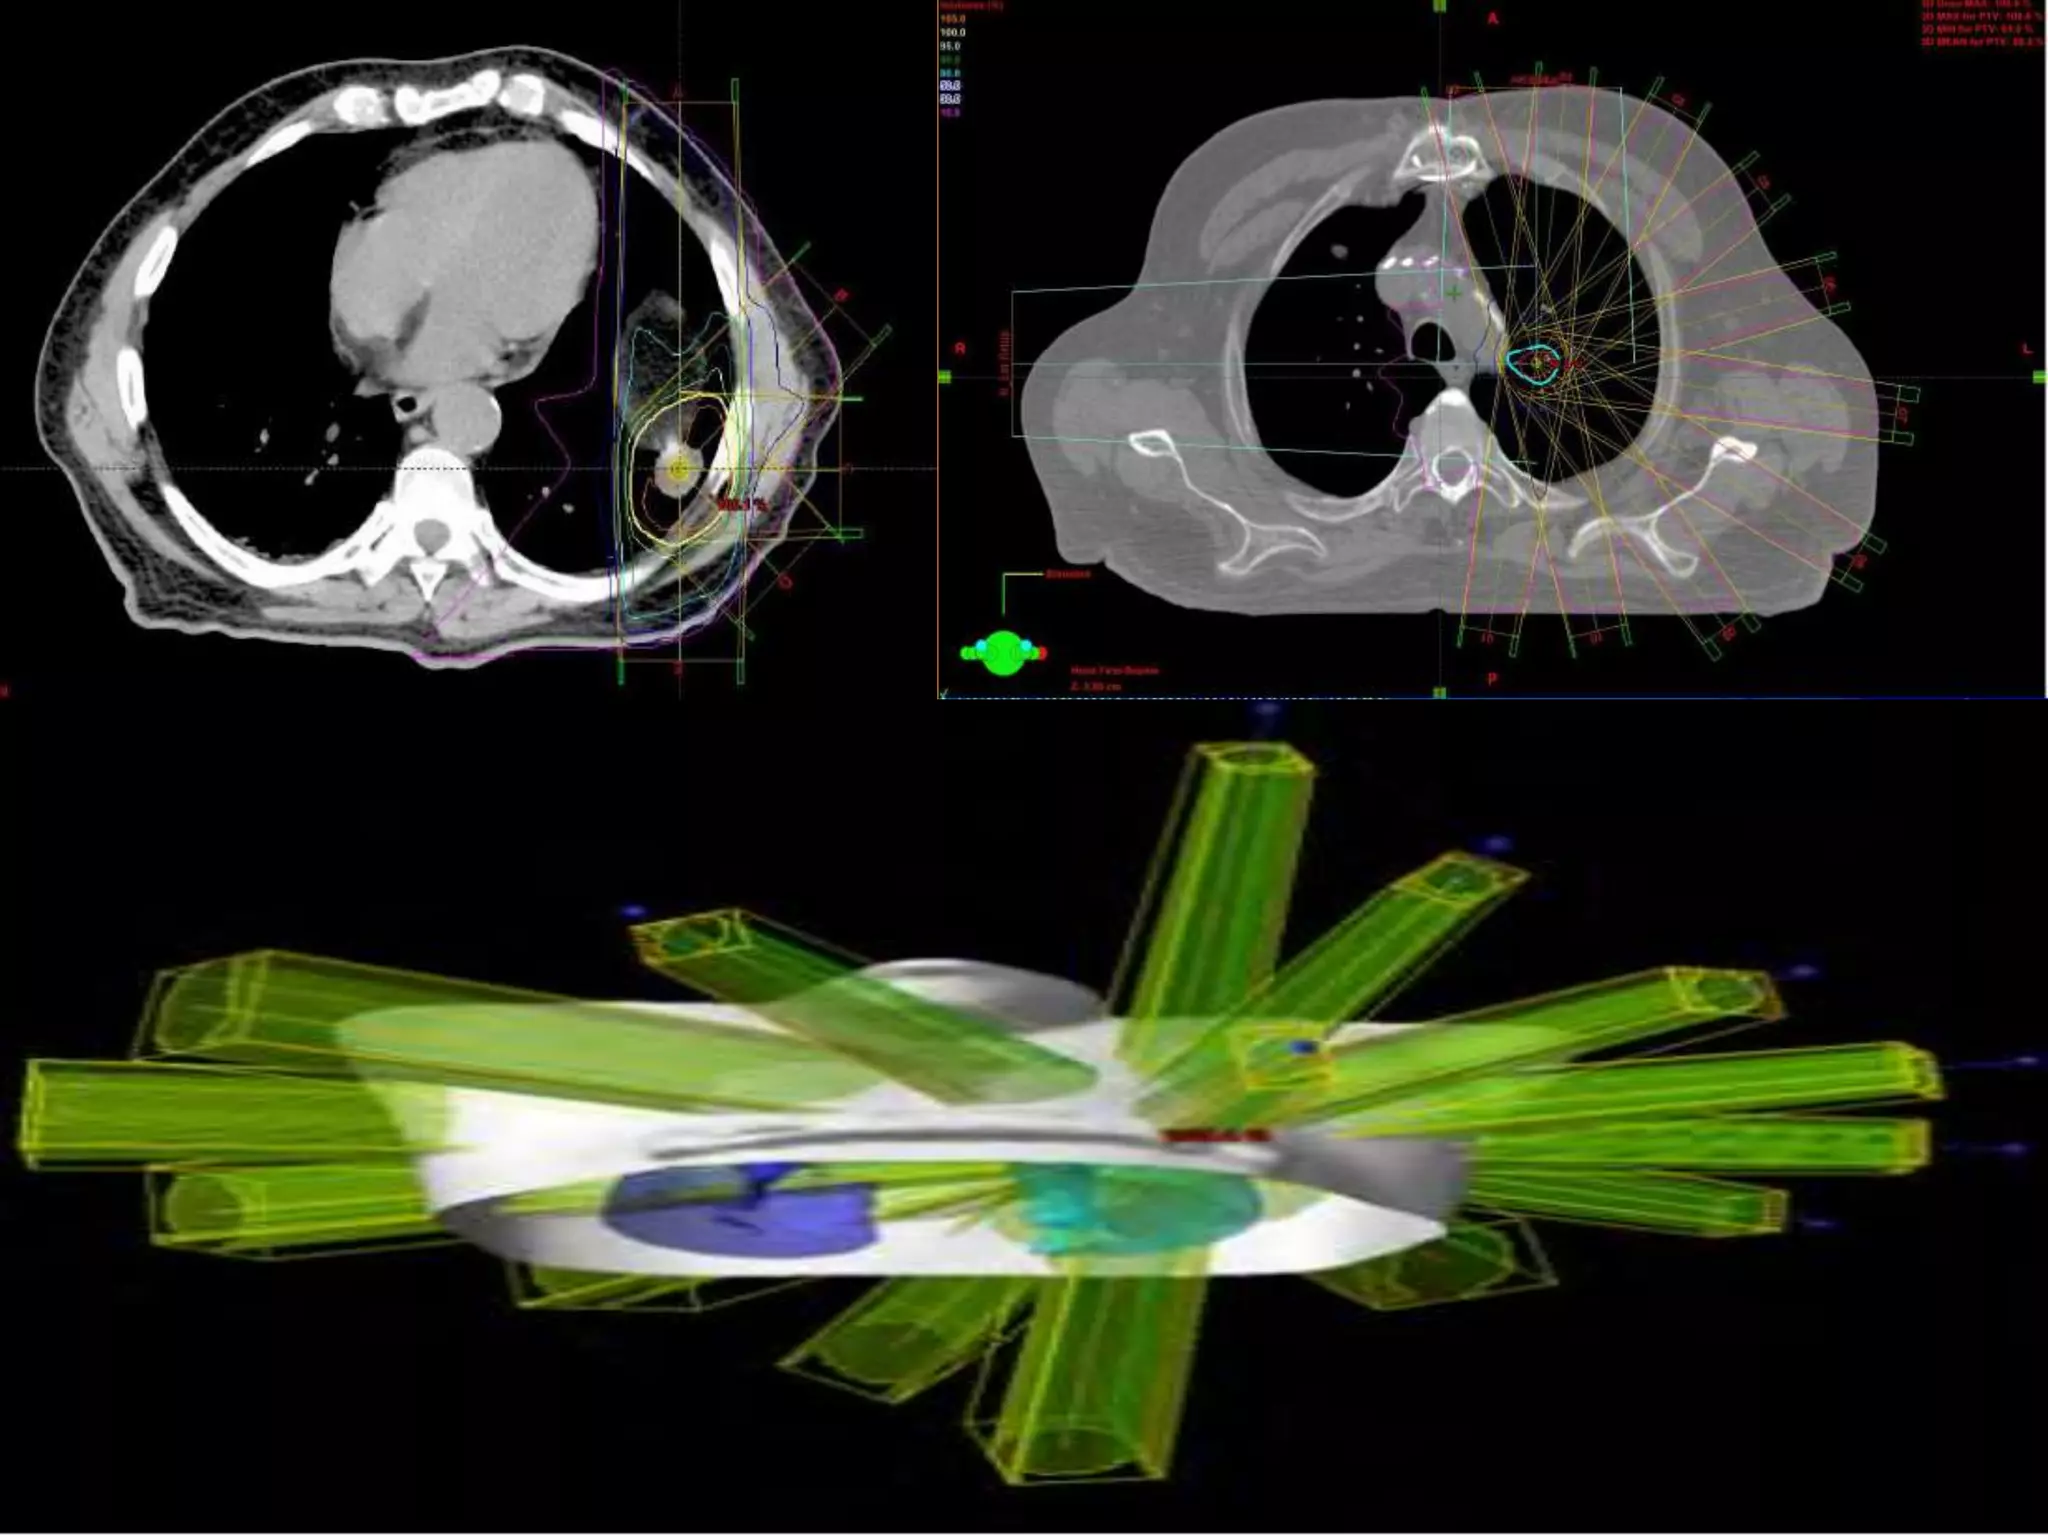

Several institutions have studied stereotactic body radiation therapy (SBRT) for primary lung cancer. Indiana University studies showed a maximum tolerated dose of 66 Gy for T2 lesions delivered over 3 fractions, with 1-year local control rates of 98%. Other studies from Aarhus University, Kyoto University, Air Force General Hospital in Beijing, and University of Marburg demonstrated 1-2 year local control rates ranging from 85-95% using SBRT dose fractions between 30-60 Gy delivered over 1 to 10 fractions.